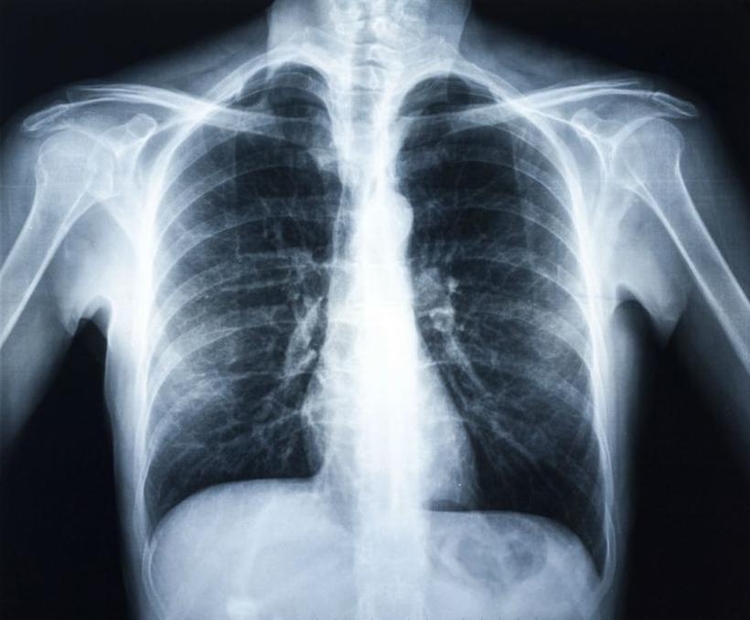

2) A pneumonia é uma doença grave?

A pneumonia é uma infecção respiratória grave, caracterizada por tosse, febre e secreção. A doença é responsável por altas taxas de internações e mortalidade, especialmente entre crianças menores de cinco anos. Cerca de 15 milhões de crianças são hospitalizadas, por ano, nos países em desenvolvimento como o Brasil. A doença também é responsável por cerca de 20% dos óbitos anuais em todo o mundo.